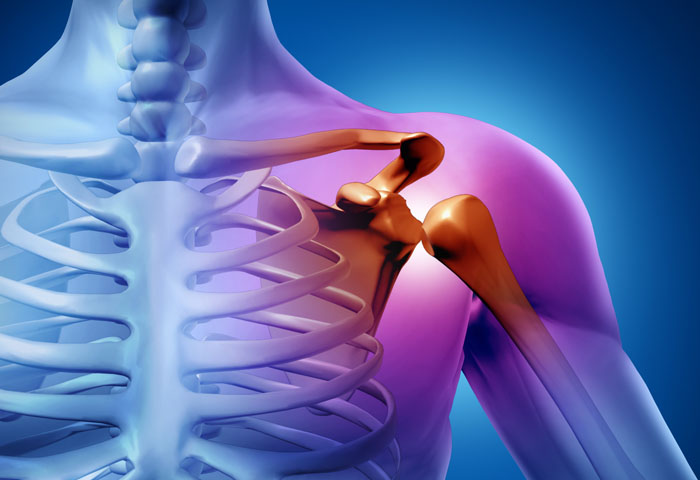

Hombros y codos sales, Dolor en el Hombro Tipos de Dolor Causas y Tratamientos Dr Michell Ruiz Especialista en Hombro Codo Rodilla. Ciudad de Mexico. Hospital Angeles Metropolitano sales

Hombro y codo Helico sales, Molestias en el hombro al empujar algo con la mano o brazo Dr Michell Ruiz Especialista en Hombro Codo Rodilla. Ciudad de Mexico. Hospital Angeles Metropolitano sales, RECONSTRUCCION ARTICULAR DE HOMBRO Y CODO OrtoClinica del Norte sales, Hombro y Codo Dr. Jose Luis Hernandez sales, Protecciones para codos y hombros nivel 2 conjunto de codos y hombros. Outlete.es sales, HOMBRO Y CODO Facebook sales, Ejercicios de hombro Traumatologia Hellin sales, Hombro y Codo Traumatologo Murcia Doctor Alonso Lison sales, HOMBRO Y CODO sales, Dolor en los hombros y codos Te digo varios ejercicios para prevenirlo tips sales, Fortalecimiento de hombros y codos sales, ANATOMIA Y FISIOLOGIA DEL SISTEMA OSEO sales, Unidad de hombro y codo Archivos Clinica DKF sales, Manejo del dolor de hombro y codo sales, HOMBRO Y CODO sales, Dr. Marlon Zeledon Ortopeda Cirugias de Codos Hombros sales, Traumatologo patologia hombro y codo Madrid Clinica MipSalud sales, Giro de hombros Codos doblados Yoga de cerca Skandha Chakra Secuencias de Yoga Beneficios Variaciones y Pronunciacion en Sanscrito Tummee sales, ORTOPEDIA HOMBRO Y CODO TRAUMATOLOGIA DR. CARLOS E. CAMPOS sales, Traumatologo para lesiones de hombro y codo en Almeria Claudio Vazquez Colomo sales, Onura Gunea SUFRES DOLOR EN TU HOMBRO O CODO IMPORTANCIA de la Estabilidad Escapular Omoplato La cintura escapular requiere de un gran trabajo de Movilidad Estabilidad y Fuerza. Y tras un sales, Hombro codo y muneca PPT sales, El Hueso entre el Hombro y el Codo y sus funciones Cirugia de hombro sales, Text Cuando su hijo tiene codo del lanzador u hombro del lanzador sales, El Hueso entre el Hombro y el Codo y sus funciones Cirugia de hombro sales, Traumatologia y Unidad de Hombro y Codo en Madrid Clinica DKF sales, Traumatologo patologia hombro y codo Madrid Clinica MipSalud sales, Terapia de mano hombro codo Academia de terapia de manos sales, Dolor en el Hombro Tipos de Dolor Causas y Tratamientos Dr Michell Ruiz Especialista en Hombro Codo Rodilla. Ciudad de Mexico. Hospital Angeles Metropolitano sales, Lo que debes saber sobre las lesiones en hombros y codos Hospital Internacional de Colombia sales, Dolor de hombro codo muneca y tratamiento OptiMMus sales, Lo que debes saber sobre las lesiones en hombros y codos Hospital Internacional de Colombia sales, Hombro y codo 1001813 VR3170L Sistema Esqueletico 3B Scientific sales, Hombro y Codo Clinica Ciudad del Mar sales, Lo que debes saber sobre las lesiones en hombros y codos Hospital Internacional de Colombia sales, Product Info: Hombros y codos sales.